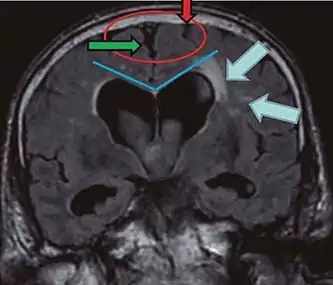

- Imaging from magnetic resonance imaging (MRI) or computed tomography (CT) is needed to demonstrate enlarged ventricles and no macroscopic obstruction to cerebrospinal fluid flow. Imaging should show an enlargement to at least one of the temporal horns of lateral ventricles, and impingement against the falx cerebri resulting in a callosal angle ≤ 90° on the coronal view, showing evidence of altered brain water content, or normal active flow (which is referred to as "flow void") at the cerebral aqueduct and fourth ventricle.

| Normal pressure hydrocephalus | Brain atrophy | |

|---|---|---|

| Preferable projection | Coronal plane at the level of the posterior commissure of the brain. | |

| Modality in this example | CT | MRI |

| CSF spaces over the convexity near the vertex (red ellipse | Narrowed convexity ("tight convexity") as well as medial cisterns | Widened vertex (red arrow) and medial cisterns (green arrow) |

| Callosal angle (blue V) | Acute angle | Obtuse angle |

| Most likely cause of leucoaraiosis (periventricular signal alterations, blue arrows |

Transependymal cerebrospinal fluid diapedesis | Vascular encephalopathy, in this case suggested by unilateral occurrence |